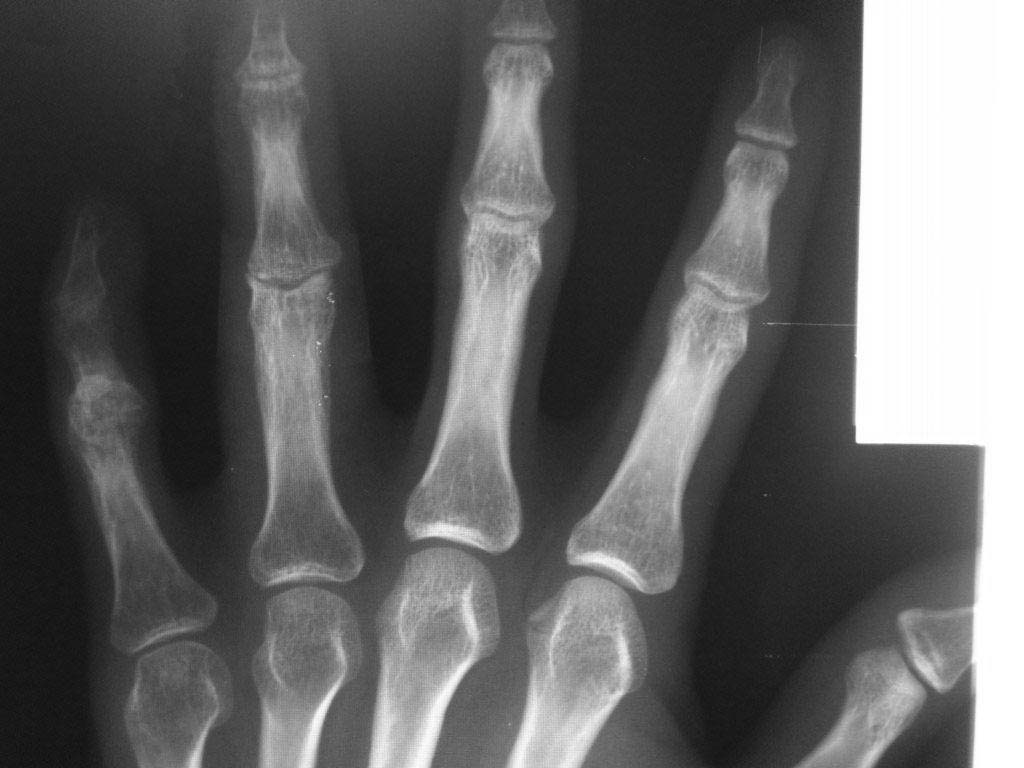

Уважаемые Коллеги! Помогите разобраться с диагнозом, из анамнеза молодой человек 27 лет, порезал руку ножом в области 4 и 5 пальцев правой кисти,

в виду особого состояния (запой), только через 2 месяца обратился в одно из травмотделений с резаной раной 4,5 пальцев правой кисти и полным разрывом сухожилий сгибателей, где был произведен неудачно поздний вторичный шов сухожилий сгибателей, после операции стойкая сгибательная контрактура этих пальцев.

Далее он обращаеется в другое травм отделение где просит врача выпрямить ему эти пальцы, что врач и сделал (артродез межфаланговых суставов в нефункциональном положении, а полностью разогнутом, прямом). После этого начинается самое интересное - уже ровно год после этих событий непрекращающее гноетечение из свищей 4 пальца на уровне проксимальной-средней фаланги.

Ему 4 раза в поликлинике и в одном из хирургических стационаров лечили консервативно и оперировали безуспешно от костного панариция.

Когда обратился ко мне на уровне средней фаланги 4 пальца, свищ по ладонной поверхности, типично как при костном панариции (остеомилите фаланги), но когда я посмотрел на снимок костей, то не увидел остеомиелита, небольшой остеопороз, но он не может быть начальным проявлением остеомилита фаланги, так как является временным переходным состоянием секвестрации фаланги и длится не более 2 недель при отсутсвии лечения, а с момента артродеза прошел уже год.

Наводит на мысль про хронический гнойный тендовагинит, но разве так долго может длиться процесс суставного панариция, да и неужели только я не вижу остеомилита? Прилагаю фото и рентгенограмму больного. Если тендовагинит, тогда буду проводить или проточно-промывное дренирование или же ваккумное дренирование после ревизии пальца, сам больной так устал, что просил ампутировать палец.